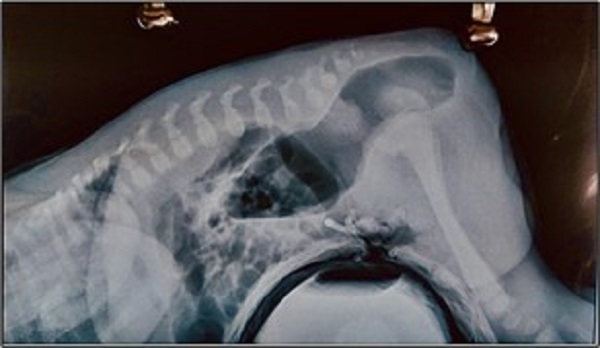

Over a period of two years (2016-2018), 35 male neonates were operated for ARM. All patients were stabilised and underwent thorough clinical assessment, complete haemogram, X-ray infantogram, Cross Table Lateral Prone (CTLP) X-ray (Fig. 1), USG abdomen with the pelvis, and 2D echocardiography. Twelve neonates underwent primary PSARP at birth. The cases were selected for primary PSARP as per the criteria summarized in (Table. 1).

Primary corrective procedure without colostomy is done with good results in female patients with vestibular fistula.[2], [10], [18] Primary PSARP in male neonates is challenging for the following reasons– managing neonates in prone jackknife position under anaesthesia; dilated rectal pouch filled with meconium causing difficulty in visualisation of the fistula. The exact distal extent of the rectal pouch and the site of the recto-urinary fistula are not delineated by distal cologram (in the absence of colostomy) as in patients undergoing a staged procedure. It is prudent to attempt neonatal primary PSARP in selected patients wherein the distal end of the rectum has crossed the levator muscle complex and is lying at/below the level of the last ossified sacral vertebra (Intermediate ARM as per Wingspread Classification).[2], [20] This can be assessed pre-operatively by a well-performed and optimally timed cross-table lateral prone X-ray and also an erect infantogram to rule out associated vertebral anomalies and a pouch colon. In these selected patients with intermediate ARM, there is the ease of dissection in virgin neonatal tissue planes. There is no fibrosis due to pouchitis as seen in older patients during the staged procedure. There is no need for rectal tapering.[2] Primary PSARP is valid and safe in such selected babies.[2]

Figure 1

Cross-table lateral prone X-ray of a male neonate suggesting an intermediate variety of anorectal malformation.

Gas shadow crossing PC line on CTLP X-ray (Intermediate ARM as per Wingspread Classification) Low ARMPouch Colon